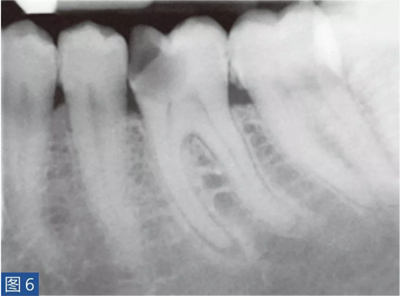

致密性骨炎(圖6 和7)是AAP 的一個變種。造成致密性骨炎的原因是,根尖周組織受到長期的持續(xù)性刺激。臨床檢查時,對敏感測試、叩診和觸診可能有反應(yīng),也可能無反應(yīng)。放射學檢查,牙齒的根尖周圍存在彌漫性的致密阻射影像。

圖6:36 牙齒CO。術(shù)前X 線片?;颊咭蜓例X36 充填物脫落而前來就診。X 線片顯示遠中根的根尖區(qū)有白色阻射影像。近中根的根尖區(qū)顯示在白色阻射區(qū)內(nèi)有透射影像。

圖7:36 牙齒CO。根管再治療12 個月后。